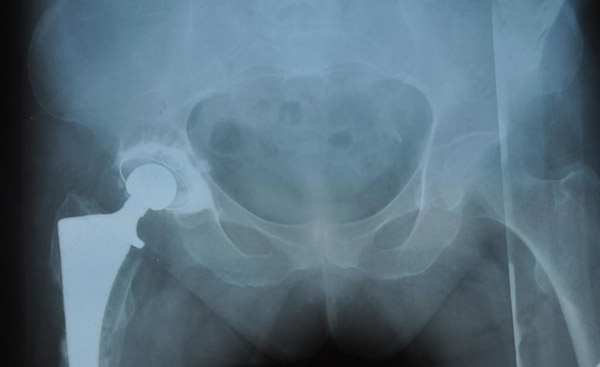

"после операции"

Выполнено 116 операций тотального эндопротезирования тазобедренных суставов.